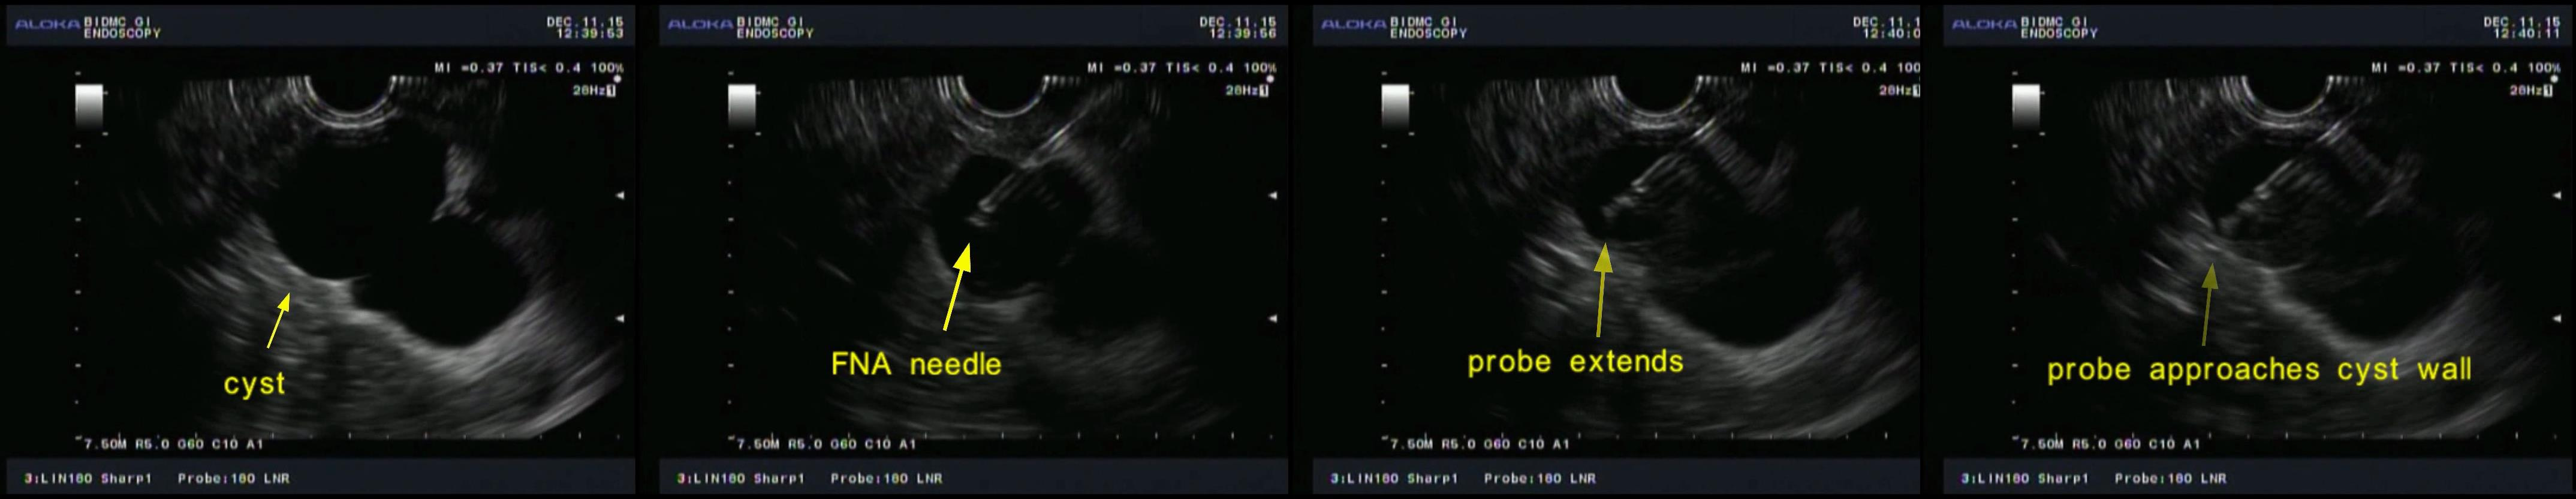

Figure 1. Cyst probe (top) is one-fifth the diameter of the esophageal probe (bottom).

Encouraged by our quite successful application of light scattering spectroscopy in the esophagus, we decided to try it for diagnosing malignancy in pancreatic cysts. The most challenging part was to develop a tiny fiber optic probe, compatible with the miniature, half millimeter in diameter, EUS-FNA needle, capable of enhancing the contribution of the light scattering signal coming from the epithelial cells. Our interdisciplinary team solved this problem by constructing a spatial gating light scattering spectroscopy (LSS) probe, which uses the fact that the backscatter signal coming from epithelial cells decreases with the distance between the source and detector fibers significantly faster than the multiple scattering signal (Fig. 1). With this probe our new LSS fine needle aspiration compatible instrument provides highly accurate in vivo identification of the malignant potential of pancreatic cysts during endoscopy (Fig 2. and Fig. 3).